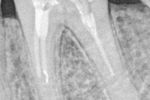

Revisionsbehandlung eines Unterkiefermolaren (37) vor geplanter Überkronung (Dr. Maik Göbbels) Download